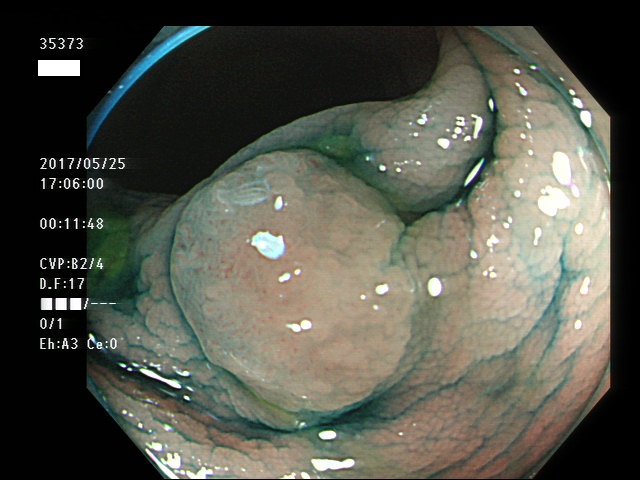

上記100名より抽出した平坦・陥凹型腺腫・SSAP(=癌化の危険が高いが見落としやすい病変)の内視鏡写真